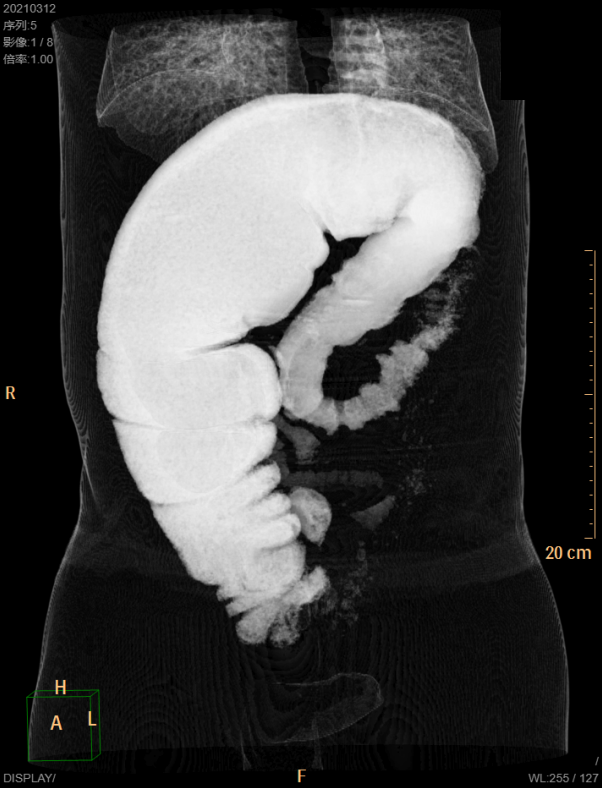

小王的检查报告揭开了“真相”。卿艳平在其腹部CT影像资料中看到了整个占满腹腔的结肠,小肠被挤到了原本不属于它的上腹部,可见多个气液平;整个结肠也扩张地非常厉害,肠腔被扩张到11.5cm,里面装满了“粑粑”,结肠袋更是消失不见,肠管管壁也因炎症渗出显示不清,而正常人肠腔最宽处也只有7.5cm。因为腹腔脏器上升挤压,引起膈肌抬高,导致双侧胸腔也存在少许积液……看到这,即使拥有丰富临床经验的卿艳平也被眼前的影像所震撼。

“便秘病人结肠扩张时常发生,扩张到这个程度并且能够引起反应性胸腔积液的患者实属罕见。”卿艳平表示。肠腔宽了4cm,看似毫不起眼,背后却蕴藏着十分凶险的危机。此外,小王的下段直肠肠腔却又是正常的,狭窄环非常明显。

巨结肠!卿艳平脑中立马闪过这个词,以上这些症状都是巨结肠典型的影像学表现。但是确诊疾病还需要进一步完善检查,排除签别诊断,还需要明确是先天性巨结肠还是成人巨结肠。主管医生依照卿艳平的要求完善了结肠输运试验、肛门直肠压力测定等专科检查,检查结果均指向先天性巨结肠。诊断先天性巨结肠的金标准是结肠活检提示肠壁Cajal细胞缺如,而且该疾病发病灶往往从直肠远端往近心端进展,治疗该疾病需要切除整个患病结肠。